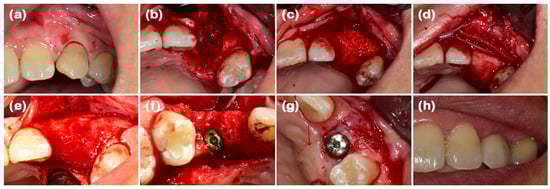

2.1. Case 1 (Single Tooth, Severe Buccal Bone Loss, and Cystic Lesion on the Extraction Region)